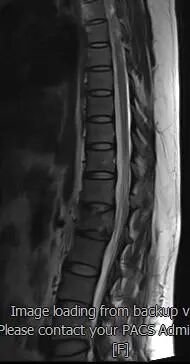

患者术前磁共振检查影像学表现:

患者术前的磁共振检查结果提示:L1椎体病变,结合病史考虑为转移癌。影像学评估提示L1椎体高信号表现,椎体高度未发生塌陷表现,椎管内容物无受压表现。患者临床腰椎功能活动受限,疼痛明显,相关生命体征平稳。